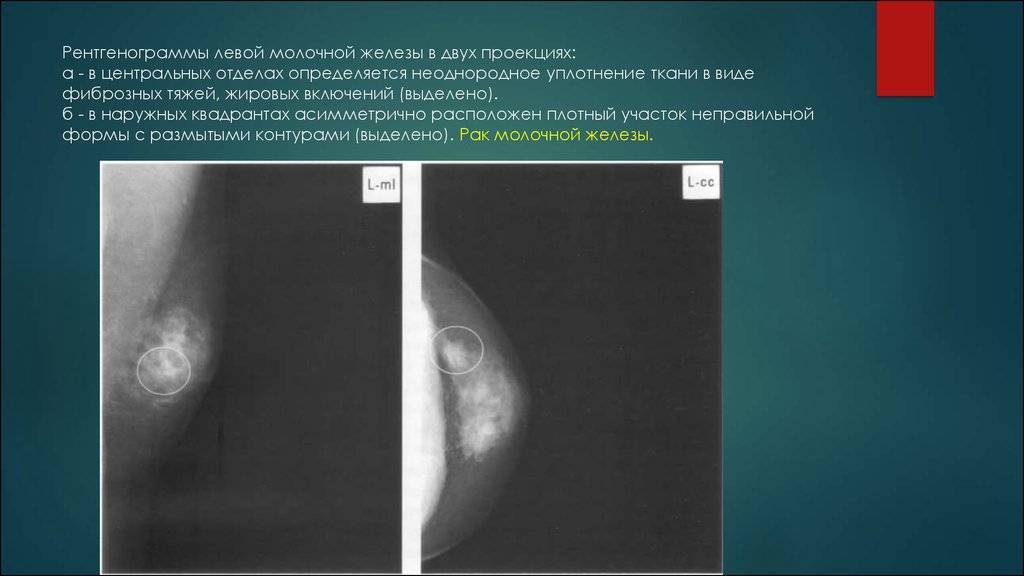

Уплотнения в груди могут быть вызваны различными причинами, включая кисты, фиброаденомы или инфекционные процессы. Важно понимать, как правильно подходить к их лечению и когда обращаться к врачу. Следующие советы помогут вам разобраться в этом вопросе и обеспечить здоровье своей груди.

Следуйте рекомендациям врача по дополнительным обследованиям, таким как УЗИ или маммография.